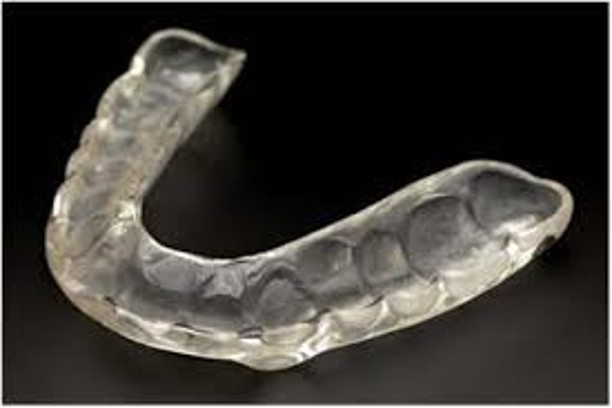

TMJ Splints

Relieves jaw pain and corrects joint alignment.

Anti-snoring Device

Helps reduce or eliminate snoring during sleep.

Bruxism Splint

Protects teeth from grinding and clenching.